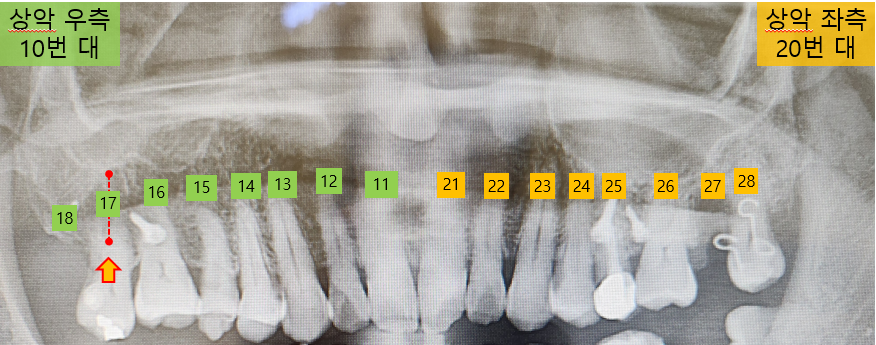

지난번 제거했던 스크루는 오른쪽 17번 치아의 잇몸 앞쪽에 삽입하였던 것입니다. 아래쪽 어금니가 빠진 후 자연스럽게 내려온 17번 치아를 임플란트 시술 전에 윗방향으로 끌어올리기 위한 교정 치료를 하고 있습니다.

이번에도 교정 장치가 부착한 부위를 깨끗하게 청소했습니다. 그런데 교정 중인 왼쪽 28번 치아를 건드릴 때마다 약간의 통증이 있음을 이야기했더니, 교정전문 의사분이 한번 더 확인을 하더군요.

확인한 결과, 28번 치아가 예상보다 빠르게 이동하면서 잇몸에 무리가 생길 수 있어, 기존에 사용하던 고무줄 대신 철사로 교정방식을 변경한다고 합니다. 아마도 당분간은 치아 이동보다는 유지하는 방식으로 조정된 것 같네요.